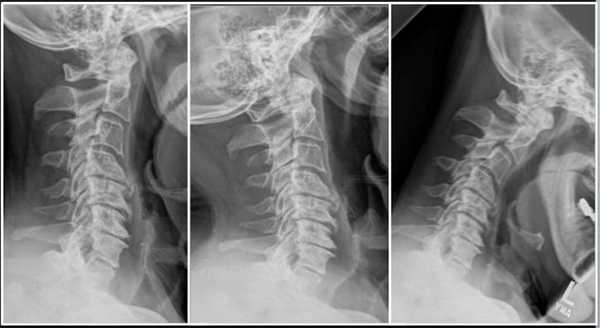

Грыжа и клювовидные остеофиты, слева рентген, справа МРТ.

Грыжа шейного отдела на КТ.